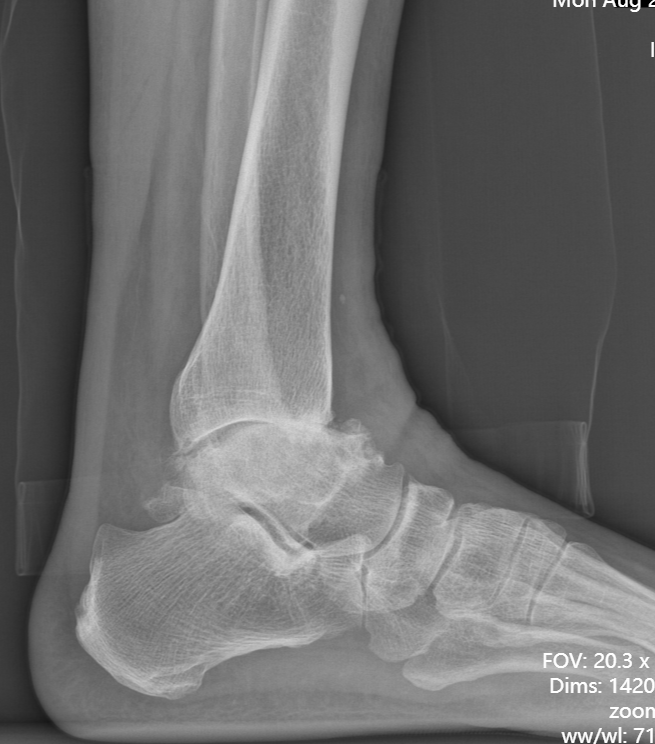

术前踝关节侧位X线

武勇主任团队给他做了3D打印导板辅助下人工全踝关节置换术。

这种手术适合踝关节病严重的患者,通过替换病变的关节结构,能帮着缓解疼痛、恢复关节活动,让老人日常走路更自在些。